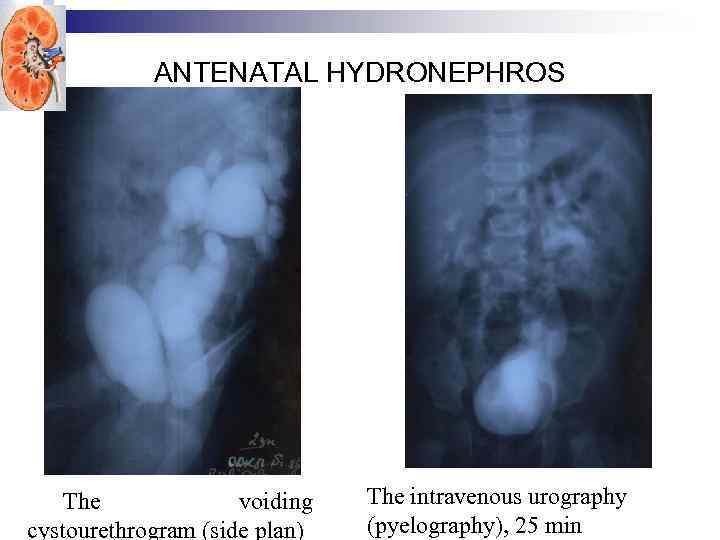

ANTENATAL HYDRONEPHROS The voiding cystourethrogram (side plan) The intravenous urography (pyelography), 25 min

ANTENATAL HYDRONEPHROS The voiding cystourethrogram (side plan) The intravenous urography (pyelography), 25 min